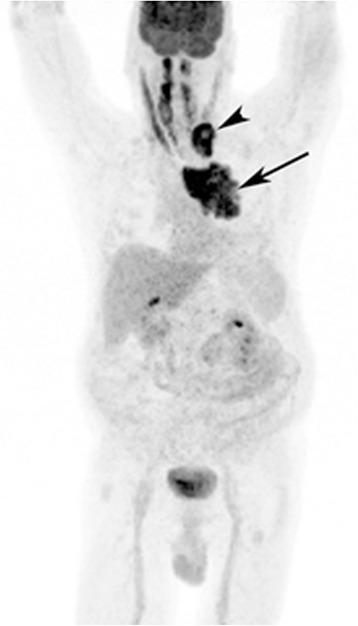

Figure 2.

Whole body PET scan using 18 F-FDG. PET scan shows a left upper thorax tumor mass (arrow) and metastases to left supraclavicular lymph nodes (arrow head).

A 62-year-old gentleman with chronic obstructive pulmonary disease (COPD) from chronic smoking presented with worsening cough and constipation for three months. Within the last year, the patient was recurrently treated for COPD exacerbations without significant clinical improvement. The patient denied having had fever, pain, nausea, vomiting, night sweats, or weight loss. Vital signs were unremarkable and pertinent findings on physical exam included mild wheezes on both lungs with decreased breath sounds over the left upper lobe, enlarged left supraclavicular lymph nodes, and hypoactive bowel sounds. Laboratory exams revealed a low sodium concentration of 130 mEq/L (normal 136–145 mEq/L), however other results were all within normal range. Computed tomography (CT) and positron emission tomography (PET) scans showed a large left upper lobe fludeoxyglucose (FDG)-avid mass (standardized uptake value (SUV) 14.3) and enlarged left supraclavicular lymph nodes with avid FDG uptake (SUV 4.0) (Figures 1 and 2). Brain magnetic resonance imaging (MRI) revealed no metastatic disease in the brain. Subsequent fine-needle aspiration of the left supraclavicular mass and immunohistochemistry staining confirmed small cell neuroendocrine cancer positive for thyroid transcription factor (TTF-1) and synaptophysin confirming the diagnosis of small cell lung cancer (SCLC). The disease was determined as extensive disease due to the fact that tumor/nodal volume was too large to be encompassed in a tolerable radiation plan. During the hospital course, the patient’s bowel movements further declined despite an aggressive bowel regimen. Ultimately, the patient developed symptoms akin to bowel obstruction and a CT scan revealed small bowel distention with multiple air-fluid levels (Figure 3). Considering possible mechanical bowel obstruction surgery was consulted and the patient underwent small bowel resection of the terminal ileum and cecum. However, no tumorous obstruction was found and histologic examination of the resected sample revealed intense lymphoplasmacytic infiltration consistent with myenteric ganglioneuritis as this is typically found in CIPO (Figure 4). Anti-Hu antibodies were positive with a titer of 1:640. Collectively, the laboratory and pathologic findings were consistent with paraneoplastic CIPO with underlying SCLC.